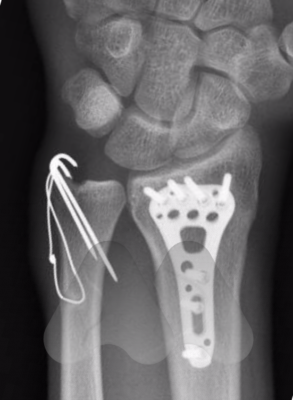

If the joint surfaces are displaced and cause a step in the normally smooth cartilage surfaces, or if the bone alignment is not acceptable, then surgery is often recommended to avoid long term dysfunction.

Surgery is normally performed under general anaesthetic as a day case admission into hospital. Surgical incisions are often made on the palm side of the wrist but additional incisions can also include the back or sides of the of the wrist, depending on the fracture.

Low profile titanium plates and screws are often used to secure the bone fragments in the correct position.